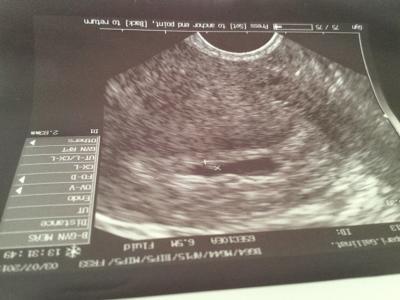

Hallo,ich war am Freitag beim Fa da war ich rechnerisch bei ssw 5+5 letzte Periode 24.5.15 Gv 5.6.15 und 7.6.15. Sie sah auf dem US leider nur die fruchthöle mit einem 1,8mm Punkt,erwartet hatte sie aber schon wenigstens den dottersack zudem fand sie freie Flüssigkeit im bauchraum Sie hat Blut abgenommen um den hcg wert zu bestimmen am Montag muss ich wieder zum US,bin sehr besorgt.Wie war es bei euch?

Bild zu Ssw 5+5 nur fruchthöle und Mini pununk - Schwanger - wer noch? Rund um die Schwangerschaft